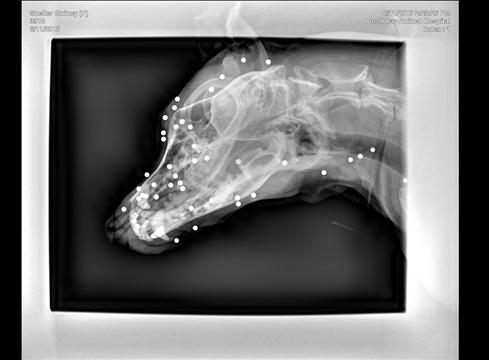

입소 후 건강검진 과정에서 피부에 혹이 발견되어 X-ray 촬영한 결과 놀랍게도 전신에 100발에 가까운 BB탄이 발견된 것이다. BB탄들은 모두 피부조직에만 머물러 있었다.

해당 유기견을 진찰한 Boothbay 데일리벳 커뮤니티병원의 수의사 딘 도메이어는 "현재는 진행 중인 상처나 통증이 없는 상태"라며 "BB탄을 제거하려는 수술 자체가 추가 외상을 불러일으킬 수 있는 상태라, 그대로 두는 것이 낫다"고 밝혔다.